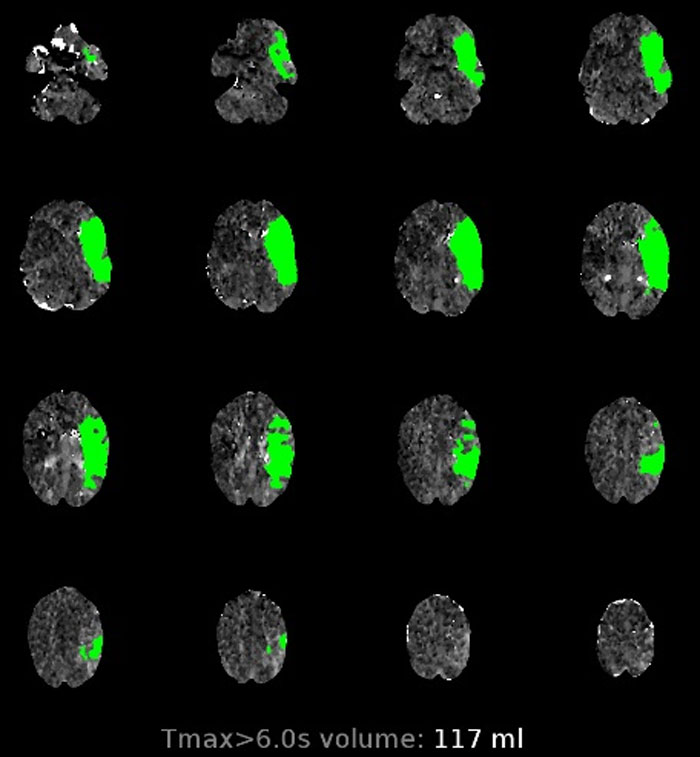

When 5-year-old Priya Galvin’s mom Mary collapsed at home from a catastrophic stroke, the girl did the only thing she could think of. She grabbed the family iPad and FaceTimed her dad, telling him that her mom wasn’t feeling well. Mary was rushed to Cork University Hospital, Ireland, where the staff there saved her life by performing a thrombectomy. Now, the entire family’s back at home and Mary is well.

According to Dr. Healy, CUH has “the busiest inpatient stroke service in Ireland.” He also mentioned that this was just one of two hospitals in the entire country that offers procedures like thrombectomies. In case you were wondering, a thrombectomy involves a specialist team removing the clot.